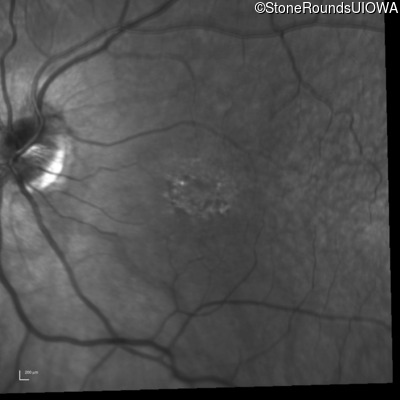

Infrared Fundus Photograph - Left - 20/125

Exemplar